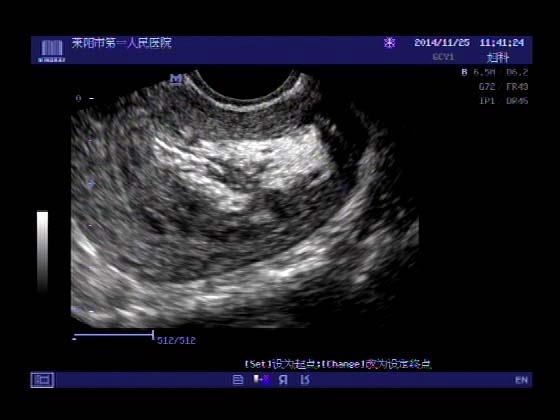

超声入门贴379---------粘膜下肌瘤(阴超的魅力)

女,43岁,月经量多3个多月,加重一个月

外院彩超检查提示:子宫后肌壁略高回声团------肌瘤?息肉?,盆腔少量积液

今天来我院检查:

巧妇难为无米之炊,经腹部超声确实很难定,阴超一目了然,乡镇医院诊断水平的提高更迫切的需要高档仪器的引进!